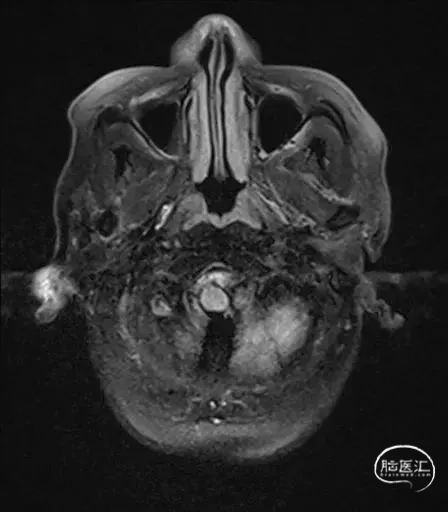

MRI提示小脑缺血性改变。

术后9天MRI:

术后CT:未见明显脑出血,双侧小脑低密度影。